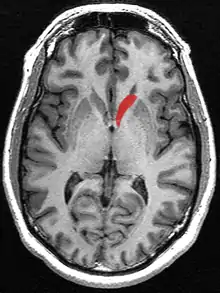

![]() Caudate nucleus (in red) shown within the brain | |